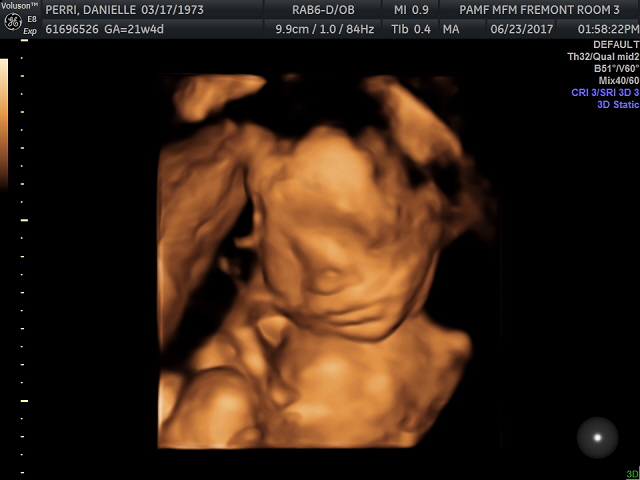

As the sonographer was unable to get all the pictures that we needed at my last anatomy screen appointment: a face profile and a few heart pictures, I had to have my second session today. The baby cooperated more than s/he had last time so she was able to get many of the heart ones right away. To my delight she also took some 3D ones letting me us see baby’s face and one hand for the first time.

The baby’s heartbeat was 139 beats a minute, a hair slower than 140 last visit and both within the healthy range. I even was given a photo of the heart chamber and the heartbeat pattern on the commemorative CD they gave afterwards.

Dr. D was the doctor this time and she said our baby was cute and healthy. As she had been told I was not choosing to learn the gender she did not look it up in my files so as not to accidentally tell me, which was sweet. Due to my age she recommended a follow up sonogram at both 30 and 36 weeks.